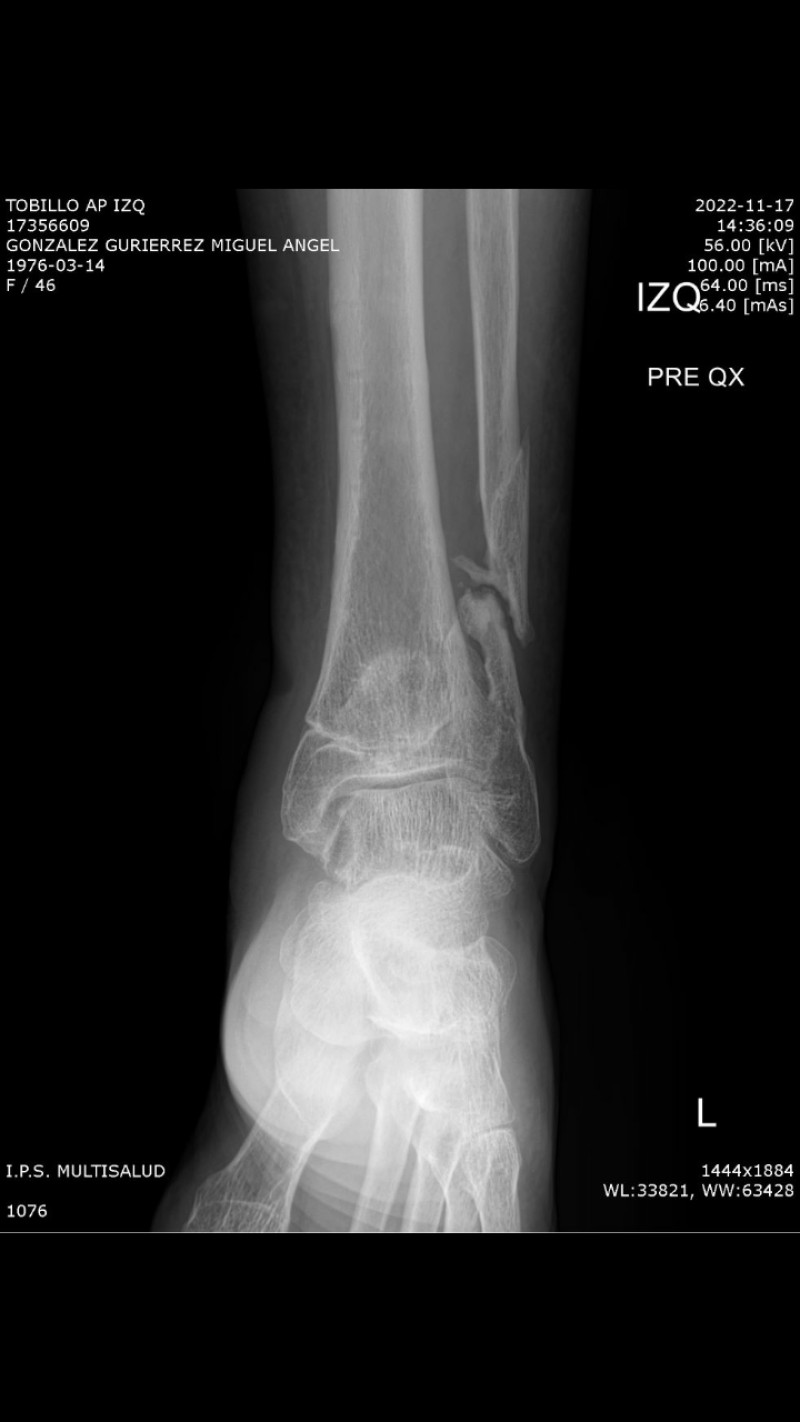

My name is Miguel González, I am 46 years old, I live in the city of Villavicencio Colombia. On November 19, 2020, I was hit from behind by a group of motorcyclists while I was going to receive a shift at my workplace. Since then my life has taken a 180 degree turn, I fractured my tibia and fibula bones, I have already had 2 surgeries, I have had bacteria in my bone, I have thyroid problems, I have not been able to return to work, I have 2 children and I am separated. I have needed psychological support. I have the 3rd leg surgery scheduled for February 25 at the La Sabana clinic in Bogotá to do grafting and reconstruction to try to have a better quality of life and recover the functionality of my foot even though I already have a 23% functional disability. I tell my story because I am looking for help/support to be able to pay for the expenses that the transfer and surgery will generate in the city of Bogotá, transportation, food, accommodation because I have to travel a day before and for what is required in the clinic and therapies. My sister always accompanies me to medical appointments and I need her for surgery since I cannot attend without a companion. If anyone can help me, I thank you with my heart, God bless you. Mi nombre es Miguel González, tengo 46 años, vivo en la ciudad de Villavicencio Colombia. El 19 de noviembre de 2020 fui arrollado por detrás por un grupo de motoristas mientras me dirigía a recibir turno en mi puesto de trabajo. Desde ese entonces mi vida ha dado un giro de 180 grados, tuve fractura de huesos tibia y peroné, ya me han realizado 2 cirugías, he tenido una bacteria en el hueso, tengo problemas en la tiroides, no he podido volver a trabajar, tengo 2 hijos y estoy separado. He necesitado apoyo psicológico. Tengo programada la 3 cirugía en la pierna para el 25 de febrero en la clínica La Sabana en Bogotá para hacer ingerto y reconstrucción para intentar tener mejor calidad de vida y recuperar la funcionalidad de mi pie aunque ya tengo un 23% de discapacidad funcional. Cuento mi historia porque busco ayuda/apoyo para poder costear los gastos que generará el traslado y la cirugía en la ciudad de Bogotá, transportes, alimentación, alojamiento porque debo viajar un día antes y para lo que me requieran en la clínica y las terapias. Mi hermana siempre me acompaña a las citas médicas y para la cirugía la necesito ya que no puedo asistir sin un acompañante. Si alguna persona puede ayudarme, le agradezco con el corazón, Dios los bendiga.